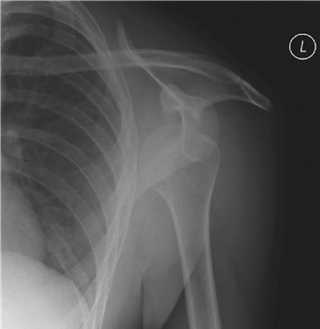

Comment on the radiograph.

This is an AP radiograph of the left shoulder showing an antero-inferior dislocation of the shoulder. One should look for associated injuries including greater tuberosity fractures, bony Bankart lesions and glenoid fractures.

Complications of anterior dislocation include axillary nerve palsy (5โ30 % ), rotator cuff tear (14โ63 % , increased in elderly), greater tuberosity (GT)/glenoid rim fracture ( > 20 % , = fi xation).

S tructures that may block reduction would include buttonholing through the capsule, biceps tendon, or bony fragments.

Why does the shoulder dislocate? What stops it normally?

The shoulder is a highly mobile joint, but at the expense of stability. When the restraints are overcome, the shoulder will dislocate. There are static and dynamic restraints.

Static restraints:

z O sseous anatomy limited to a third of the head on the glenoidโ d epth increased by labrum

(โผ50 % ) z Negative pressure inside joint z Capsular thickenings โ superior glenohumeral ligament (SGHL)/middle glenohumeral ligament (MGHL)/inferior glenohumeral ligament (IGHL) (most important โ hammock analogy) Dynamic restraints:

z Rotator cuff muscles z Long head (LH) of biceps tendon

The A&E staff have tried to reduce this without successโ talk me through how you would reduce this dislocation.

The patient has his arm externally rotated and abducted with loss of the deltoid contour. If the patient was still sedated I would attempt one further reduction in A&E. If unable to reduce I would mobilize my theatre team and anaesthetist to perform a reduction under GA:

z Hippocratic method โ foot in axilla on humeral head, traction on abducted arm z Kocher method of reduction โ flex elbow 90 ยฐ , arm in neutral, and then ER slowly until you hear a clunk of reduction. If does not reduce, flex shoulder, slowly internal rotate, and fully adduct across chest (no traction)

z Modified Stimpson โ hanging weight prone

If the patient was young I would splint them in an ER position for the fi rst 2 weeks then begin a mobilization programme guided by the physiotherapists.

What is the risk of this shoulder causing problems again?

The re-dislocation rate is proportional to the age at fi rst dislocation.

There is a tendency to be more aggressive in the management of young, fi rst-time dislocations. Use MRI arthrograms [look for Bankart ( ยฑ bony)/capsular tear/HillโSachs lesion] or early EUA and arthroscopy to look for and repair Bankart lesions (labral detachment between 3 and 9 oโclock).

What approach would you do for an open reduction?

Deltopectoral. (See answer to Viva 2.)